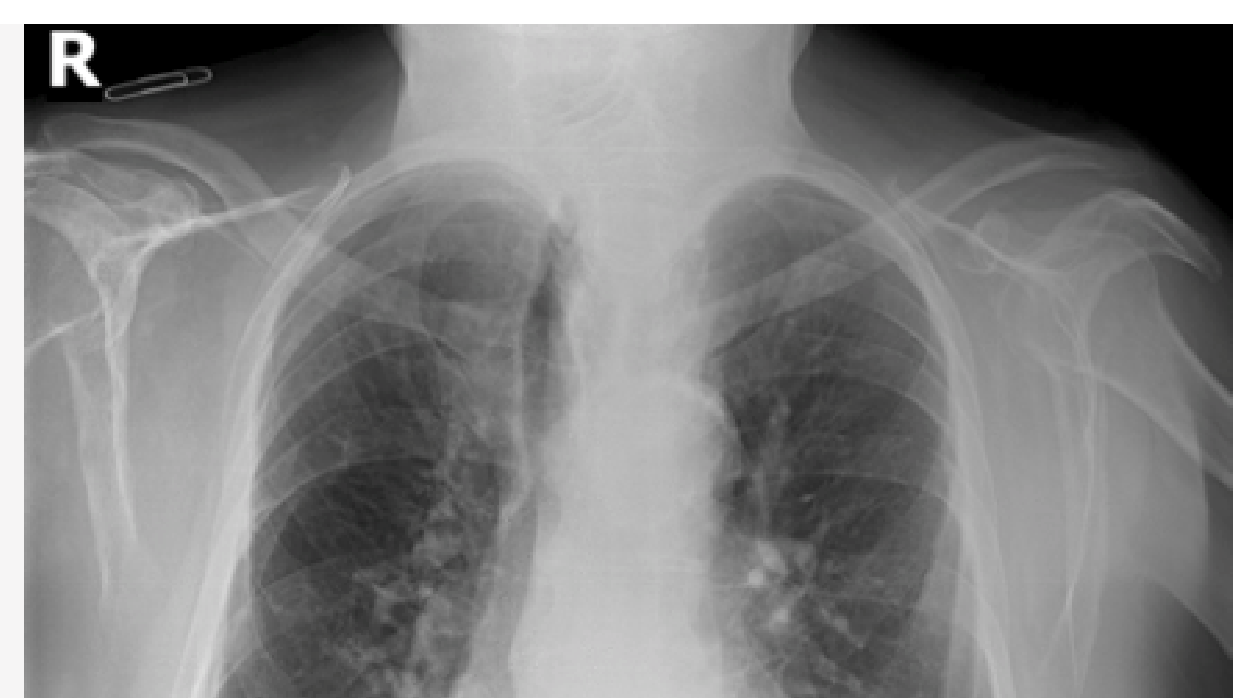

Personal investigador de la Unidad Mixta en Imagen Biomédica de FISABIO (Fundació per al Foment de la Investigació Sanitària i Biomèdica de la Comunitat Valenciana) y el CIPF (Centro de Investigación Príncipe Felipe) ha creado una base de datos en abierto para aplicar Inteligencia Artificial en la detección precoz de neumonía provocada por el COVID-19 a partir de una radiografía simple de tórax.

La base de datos recoge imágenes de radiografía de tórax (PadChest), perteneciente al Banco de Imágenes de la Comunidad Valenciana (BIMCV) . En una primera fase, los investigadores/han realizado el proceso de construcción, mantenimiento y recopilación de las imágenes, organizadas por patologías relacionadas con neumonía.

La organización de esta información pretende ayudar al desarrollo de herramientas de diagnóstico simples, rápidas y efectivas, para que los profesionales sanitarios puedan realizar una detección temprana de la neumonía causada por COVID-19 .

Según explican los responsables de la iniciativa, «debido a la alta disponibilidad y la asequibilidad de los datos de rayos X convencionales, ampliamente utilizados y más accesibles que las tomografías computarizadas , los sistemas de Inteligencia Artificial podrían ser una herramienta esencial para minimizar y agilizar la carga de trabajo en los entornos clínicos».

Para el desarrollo de esta herramienta, el personal investigador ha tenido en cuenta los recientes estudios realizados por investigadores chinos cuyos resultados detallan las características clínicas y paraclínicas de COVID-19 . Según los responsables de la iniciativa, «estos estudios han demostrado que el COVID-19 presenta patrones característicos únicos en imágenes de rayos X de tórax y tomografía computarizada (Ng et al, 2020 / Ng, Ming-Yen, et al. 2020)».